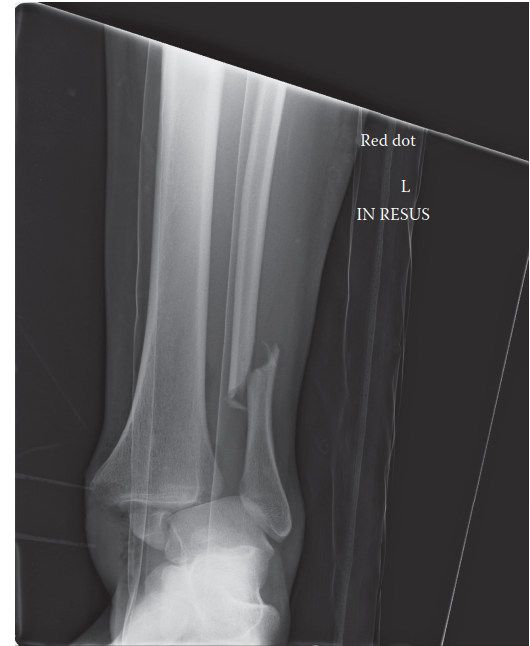

Can you describe the radiograph? This is an AP radiograph of the left ankle showing a fracture dislocation. T…